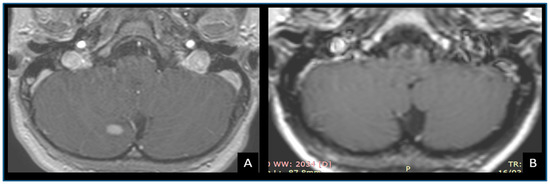

- Ellis, M.J.; Cheshier, S.; Sharma, S.; Armstrong, D.; Hawkins, C.; Bouffet, E.; Rutka, J.T.; Taylor, M.D. Intracerebral malignant peripheral nerve sheath tumor in a child with neurofibromatosis type 1 and middle cerebral artery aneurysm treated with endovascular coil embolization: Case report. J. Neurosurg. Pediatr. 2011, 8, 346–352. [Google Scholar] [CrossRef] [PubMed]

- Oztanir, N.; Emmez, H.; Aytar, M.H.; Dogan, M.; Kaymaz, M.; Baykaner, M.K. Malignant intracerebral giant nerve sheath tumor in a 14-month-old girl with neurofibromatosis type 1: A case report. Child’s Nerv. Syst. 2009, 25, 253–256. [Google Scholar] [CrossRef] [PubMed]

- Casadei, G.P.; Komori, T.; Scheithauer, B.W.; Miller, G.M.; Parisi, J.E.; Kelly, P.J. Intracranial parenchymal schwannoma: A clinicopathological and neuroimaging study of nine cases. J. Neurosurg. 1993, 79, 217–222. [Google Scholar] [CrossRef] [PubMed]

- Beauchesne, P.; Mosnier, J.F.; Schmitt, T.; Brunon, J. Malignant nerve sheath tumor of the right cerebral peduncle: Case report. Neurosurgery 2004, 54, 500–504. [Google Scholar] [CrossRef] [PubMed]

- Gao, Y.; Qin, Z.; Li, D.; Yu, W.; Sun, L.; Liu, N.; Zhao, C.; Hu, Y.; Sun, D.; Jin, X. Intracerebral schwannoma: A case report and literature review. Oncol. Lett. 2018, 16, 2501–2510. [Google Scholar] [CrossRef]

- Patankar, A.P.; Sheth, J.H. Intracranial malignant nerve sheath tumor in the middle cranial fossa: A rare case report with review of literature. Asian J Neurosurg. 2019, 14, 922. [Google Scholar] [CrossRef]

- Wong, S.T.; Moes, G.; Ernest, K.; Zovickian, J.; Kim, J.Y.; Pang, D. Innervation of the brain, intracerebral Schwann cells and intracerebral and intraventricular schwannomas. Child’s Nerv. Syst. 2014, 30, 815–824. [Google Scholar] [CrossRef]